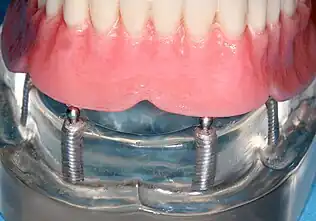

Implant-supported overdenture

A removable implant supported denture (also an implant supported overdenture[18]: 31 ) is a removable prosthesis which replaces teeth, using implants to improve support, retention and stability. They are most commonly complete dentures (as opposed to partial), used to restore edentulous dental arches.[12] The dental prosthesis can be disconnected from the implant abutments with finger pressure by the wearer. To enable this, the abutment is shaped as a small connector (a button, ball, bar or magnet) which can be connected to analogous adapters in the underside of the dental prosthesis.

Prosthetic procedures for removable dentures

When a removable denture is worn, retainers to hold the denture in place can be either custom made or "off-the-shelf" (stock) abutments. When custom retainers are used, four or more implant fixtures are placed and an impression of the implants is taken and a dental lab creates a custom metal bar with attachments to hold the denture in place. Significant retention can be created with multiple attachments and the use of semi-precision attachments (such as a small diameter pin that pushes through the denture and into the bar) which allows for little or no movement in the denture, but it remains removable.[18]: 33–34 However, the same four implants angled in such a way to distribute occlusal forces may be able to safely hold a fixed denture in place with comparable costs and number of procedures giving the denture wearer a fixed solution.[61]

Alternatively, stock abutments are used to retain dentures using a male-adapter attached to the implant and a female adapter in the denture. Two common types of adapters are the ball-and-socket style retainer and the button-style adapter. These types of stock abutments allow movement of the denture, but enough retention to improve the quality of life for denture wearers, compared to conventional dentures.[62] Regardless of the type of adapter, the female portion of the adapter that is housed in the denture will require periodic replacement, however the number and adapter type does not seem to affect patient satisfaction with the prosthetic for various removable alternatives.[63]